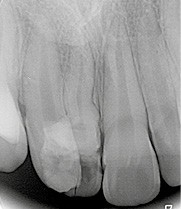

Son incisive centrale supérieure droite (11) présente un défaut de structure amélaire sévère, compromettant une technique restaurative pérenne a minima. L’examen de la panoramique (fig. 1e) et de la radiographie rétroalvéolaire de 11 (fig. 1f) objective une fracture coronaire verticale, ainsi qu’une racine grêle et courbe, peut-être en rapport avec un ancien traumatisme [1]. Le rapport couronne clinique/racine clinique est défavorable.